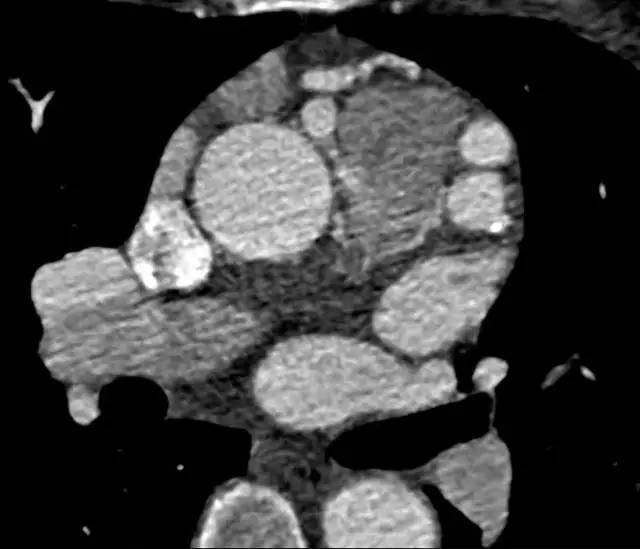

冠状动脉血管造影(CTA)回顾性心电门控扫描结果如下:

图 2

冠状动脉 CTA 是诊断该病理想的检查方法,轴位(图 1,2)及最大密度投影(图 3)CTA 显示右冠状动脉起源于主肺动脉。左冠状动脉主干显著代偿性扩张(图 4)。右冠状动脉未见狭窄及肌桥。左心室肥厚,左室射血分数为 55%。